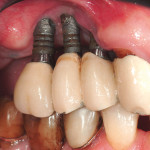

Ricostruzione della volumetria ossea crestale mediante innesto di particolato cortico-midollare: caso...

Riassunto

Le attuali conoscenze sulla guarigione, la biologia e il destino dell’alveolo post-estrattivo hanno permesso di poter risolvere con margini di accettabile predicibilità le condizioni...